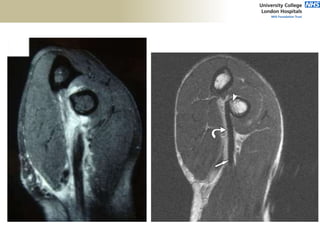

FABS MRI